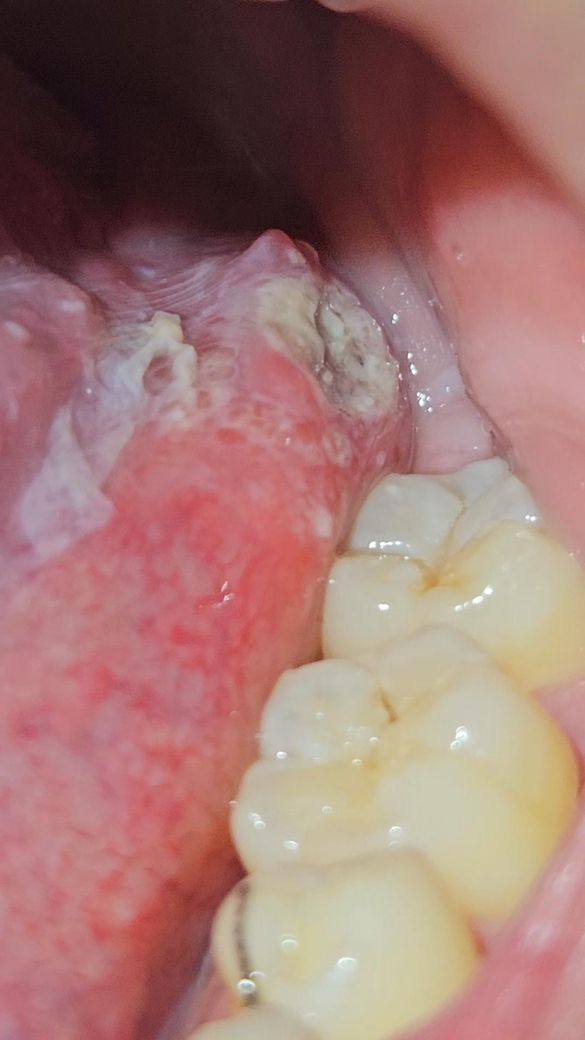

혀 밑 구내염 크기가 이래도 되는건가요?

혀밑에 작게 났던 구내염을 5일간 알보을 꾸준히 발랐는데도 작아지킨 커녕 점점 더 파이고 크기가 커졌습니다 근처 이비인후과에 가야할까요? 가면 어떤 치료를 받을까요?

올려주신 사진으로 미루어 구내염에 준하여 알보칠을 사용하였으나 더 악화되었다면 이비인후과 진료를 받아 보시는 것이 좋겠습니다.

• 구내염이 크게 생기는 것은 발생 불가능한 현상은 아니지만 점점 커지고 악화되고 있는 양상이라면 혹시 모르므로 이비인후과 진료 및 치료를 받아보시는 것이 좋겠습니다. 당장 어떠한 치료가 진행될지 알 수는 없지만 감별 진단을 위해서 진료를 받으시는 것이 필요해 보이며, 아무래도 스테로이드 약물 등을 처방 받아서 복용을 해보는 것이 도움이 될 수도 있어 보입니다.